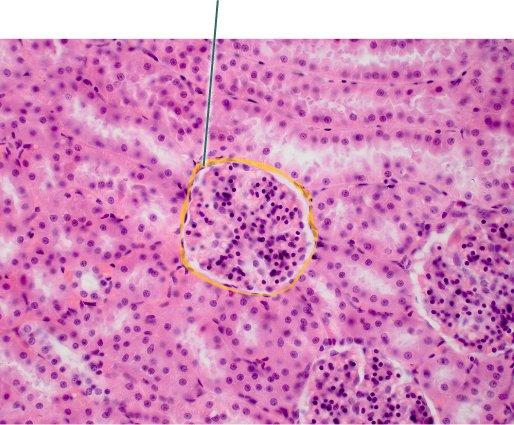

Which structure is highlighted?

reticular fibers

collagenous trabaculae

lymphocytes

macrophages

reticular fibers

Which component of the connective tissue in this field of view is

highlighted?

chondrocytes

extracellular matrix

lacunae

collagen fibers

extracellular matrix